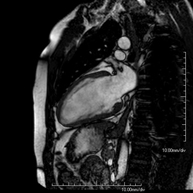

- Coronary MRI

This non-invasive diagnostic test yields morphological and functional information about the heart and adjacent structures. In this way, different congenital and acquired pathologies can be diagnosed, or checks can be carried out on patients with previously known pathologies. In the vast majority of cases, intravenous contrast (gadolinium) is required to complete the study. This type of contrast rarely causes adverse reactions. During the test, the technician will ask the patient to hold their breath several times for 10–15 seconds to obtain the clearest images possible. No prior preparation is required by the patient. The test lasts approximately 45–60 minutes. It is not recommended for patients with pacemakers. Patients should nevertheless inform the doctor if they have metal implants and/or surgical clips.